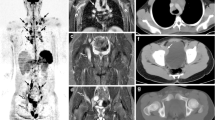

The sensitivity and specificity of combining short-axis-diameter ≥10-mm size threshold applied to all nodes, followed by ADC cut-off values of 0.77, 1.15 and 1.79×10−3 mm2 s−1 to 5- to 9-mm lymph nodes for both readers, are given in Table 4. Figures 7 and 8 demonstrate examples of true-positive and false-positive whole-body MRI nodal classification using the combined short-axis diameter and ADC threshold.

Images in a 15-year-old boy with Hodgkin lymphoma. a Axial 18flourine-2-fluoro-2-deoxyglucose (FDG) positron emission tomography (PET)/CT shows a positive left axillary node (arrow). b Axial short tau inversion recovery half-Fourier acquisition single-shot turbo-spin-echo (repetition time/echo time [TR/TE] = 800/60 ms) MR image demonstrates an 8-mm short-axis-diameter left axillary node (arrow). c Axial diffusion-weighted imaging (DWI; b=500 s/mm2; TR/TE=4,900/66 ms) demonstrates an 8-mm short-axis-diameter left axillary node. These findings would result in false-negative nodal classification according to the threshold of short-axis diameter ≥10 mm. d Apparent diffusion coefficient (ADC) map demonstrates the same left axillary node (arrow) with an ADC of 0.8×10−3 mm2 s−1. The node was deemed positive on whole-body MRI using the combined short-axis diameter ≥10 mm and ADC cut-off of <1.15×10−3 mm2 s−1 classification — a true-positive result compared with using the FDG PET/CT reference

Images in a 16-year-old girl with Hodgkin lymphoma. a18Flourine-2-fluoro-2-deoxyglucose (FDG) positron emission tomography (PET)/CT is deemed negative for left cervical nodal involvement. b Axial short tau inversion recovery half-Fourier-acquisition single-shot turbo-spin-echo (repetition time/echo time [TR/TE] = 800/60 ms) MR image demonstrates a 5-mm short-axis-diameter left cervical node (arrow). c Axial diffusion-weighted imaging (DWI; b=500 s/mm2; TR/TE=4,900/66 ms) demonstrates a 5-mm short-axis-diameter left cervical node (arrow). These findings would result in true-negative nodal classification. d Apparent diffusion coefficient (ADC) map demonstrates the same left cervical node (arrow) with ADC of 0.9×10−3 mm2 s−1. The node was deemed positive on whole-body MRI by combined short-axis diameter ≥10 mm and ADC cut-off value of <1.15×10−3 mm2 s−1 classification — a false-positive result compared with using the FDG PET/CT reference